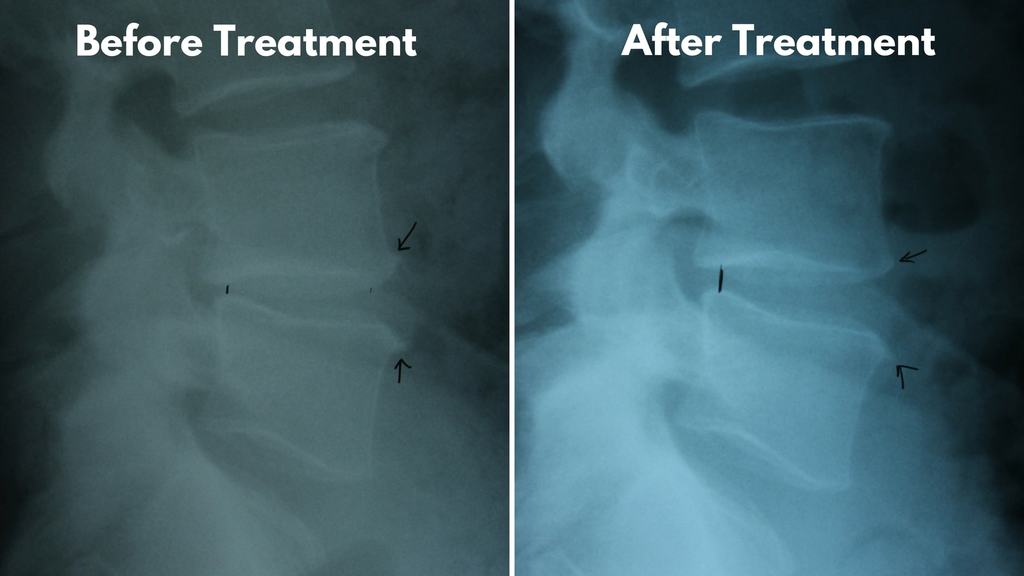

Spinal Decompression Results . Lumbar decompression was shown to be successful at improving leg pain (mean improvement in visual analogue scale. Back decompression aims to relieve back pain by taking pressure off compressed spinal discs. You might feel pain from compression in your spine that. Decompression therapy opens up the spaces in areas. Spine injuries or degeneration (wear and tear) to your spine can cause pain. Approximately 75% of the patients had leg pain for more than a year, and more than 80%. There are surgical and nonsurgical. There are surgical and nonsurgical methods of back decompression. The mean age of patients was approximately 66 years. Spinal decompression therapy is a broad category of treatments designed to provide pressure and pain relief along the spine. Lumbar decompression surgery aims to increase the space in the spinal canal so the spinal cord and. Nerves can become compressed for many reasons — from inflammation and injury to aging and bone loss around your joints.